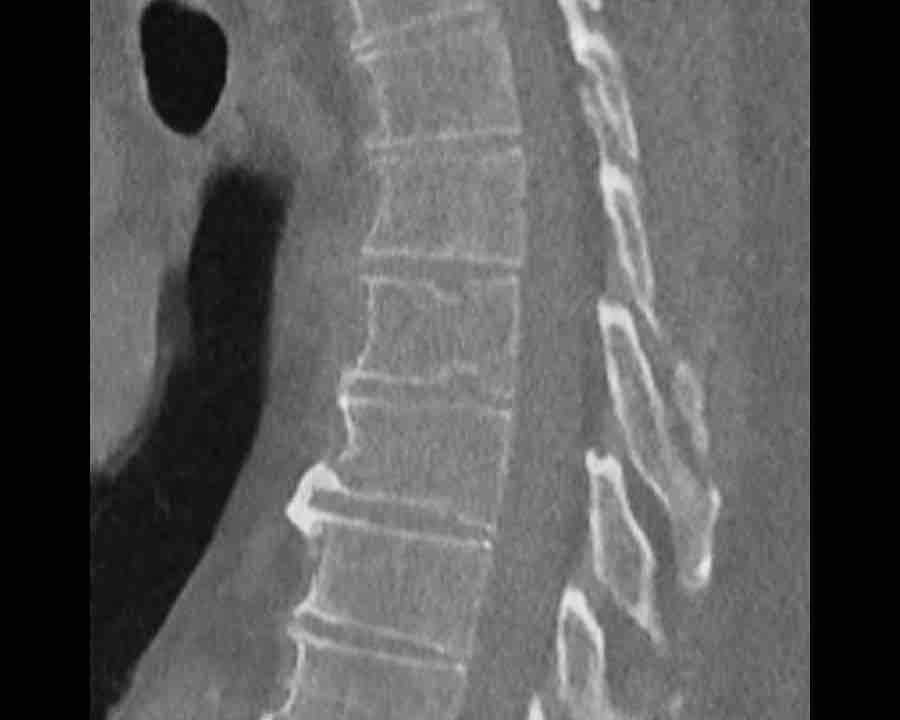

Scroll through images.

What are the findings?

Findings

- C injury? No.

- Signs of a rigid spine?

Yes (DISH), so a B3 injury is very likely. - A subtle fracture on the anterior vertebral body (arrows).

- No separation, probably due to positioning of patient in the scanner

Conclusion

Injury type B3.